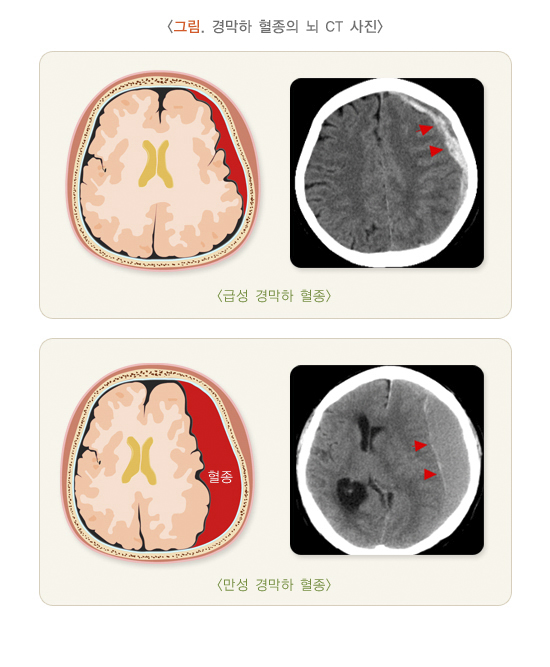

경막하 출혈은 뇌를 싸고 있는 뇌경막 아래쪽으로 혈종이 고인 것을 말합니다. 경막하 출혈은 증상 발현 및 CT 소견에 따라 급성 경막하 출혈과 만성 경막하 출혈로 구분합니다.

급성 경막하 출혈은 외상 뇌출혈 가운데 가장 위중한 경우로 보통 사망률이 60%를 넘습니다. 설령 사망하지 않더라도 중증의 후유 장애를 남기는 아주 위험한 뇌출혈입니다. 가장 흔한 원인은 추락 사고, 폭행, 교통사고 등이 있습니다. 경막하 출혈의 두께가 1 cm를 넘거나 이로 인한 정중선 이동이 발생하면서 의식 저하가 동반되는 경우 응급으로 혈종을 제거하고 감압 개두술을 시행하여야 합니다. 혈종이 잘 제거되더라도 경막하 혈종이 발생한 경우는 혈종이 발생한 아래쪽 부위에 뇌손상을 심하게 동반하는 경우가 많아 수술적 치료 후에도 사망에 이르기도 하며, 생존하더라도 후유증으로 인해 사고 이전의 정상적인 생활로 돌아갈 가능성은 거의 없습니다.

만성 경막하 출혈은 주로 노년층에서 관찰되며, 알콜 중독, 간질 환자, 항응고제 혹은 항혈소판제 복약, 치매 환자 등에서 자주 발생하는 것으로 알려져 있습니다. 워낙 경미한 두부 외상으로 인해 발생하기에 50%의 환자들은 자기가 언제 다쳤는지를 기억하지 못합니다. 두부 외상 후 약 3주 내외가 경과한 이후 진단되는 것이 일반적이며, 한쪽의 편마비, 언어 장애 혹은 인지 기능 저하의 증상을 보여 뇌졸중으로 오인하여 치료 시기를 놓치는 경우도 종종 있습니다. 증상이 동반되거나 출혈의 두께가 1 cm을 넘거나 이로 인한 정중선 이동이 보이면 수술을 계획합니다. 만성 경막하 혈종의 수술은 두개골에 작은 구멍을 내고 그 구멍으로 출혈을 빼주는 천공 배액술 만으로도 대부분 회복이 잘 됩니다. 하지만 양측성이거나 70세 이상의 노인, 항응고제 혹은 항혈소판제 복약, 알콜 중독의 경우에는 재발률이 25%까지 보고되고 있어 주의를 필요로 합니다. 금주가 필수적이며, 반복적으로 넘어지는 경우 그 원인을 감별하기 위한 신경과 진료가 필요하며, 낙상을 예방하는 것이 중요합니다.